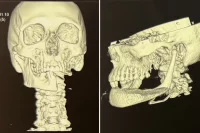

Как сообщили в донском минздраве, врачи провели уникальную операцию пациентке с аномально большой опухолью. Доктора впервые в своей практике столкнулись со столь огромным новообразованием. Размер его достиг тысячи кубических сантиметров. Опухоль не только стала причиной плохого самочувствия, но и существенно сказалась на качестве жизни. Подробности выяснил rostov.aif.ru.

В груди росло новообразование объёмом почти 1000 кубических сантиметров. Для сравнения: нормальная щитовидная железа у женщин — не более 18 кубических см. То есть орган разросся в 55 раз!

Парадокс, но при таких размерах шея у женщины выглядела вполне обычно. Почему?

«Практически вся патологическая железа находилась в так называемом средостении грудной клетки, сдавливая в том числе крупные кровеносные сосуды. За счёт сдавления внутренних вен пошло перераспределение кровотока: наружные вены выпирали из-под кожи», — пояснил Станислав Викторович.